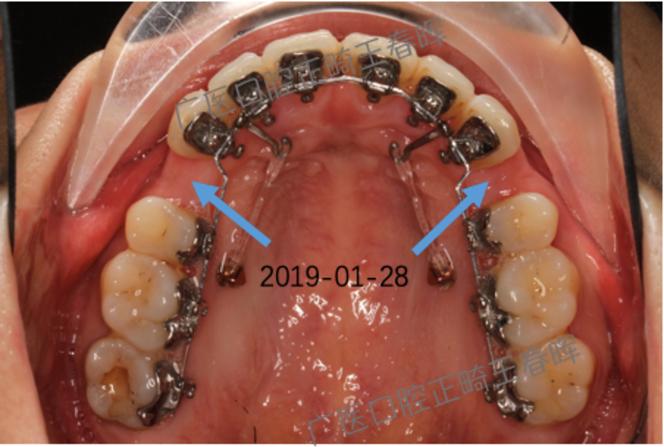

- 托槽粘接:个性化托槽制作完成后(通常4-6周),医生进行粘接,调整托槽角度,确保牙齿按计划移动。

- 定期复诊:每4-6周复诊一次,医生检查牙齿移动情况,更换弓丝,调整托槽,期间可能出现口腔溃疡、发音不适等,需及时沟通。